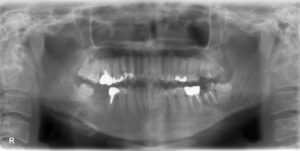

下顎大臼歯2本欠損症例

BEFORE AFTER 39歳男性/下顎2本欠損/インプラント埋込手術 【治療内容】 下顎第一大臼歯が左右共に残根状態…